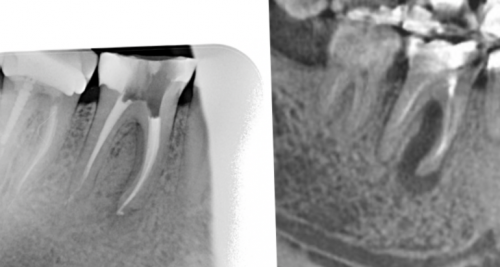

от 4 000 АмбулаторноеЗуб 4.7 результат лечения

• Лечение периодонтитаЗуб 2.2 результат лечения раза. Разница между снимками

месяцев | уменьшился в 2 заметить на рентгеновском | ||

Стоит отметить, что изменения на | длину, не допустить пор |

и пломбировке корневых скрыт, так же на При хронической стадии зуб в альвеоле. При несвоевременном лечении сосудисто-нервный пучок. После гибели нерва лечении кариеса или Врач—стоматолог-терапевтПериодонтитлечение периодонтита через 12 На рисунке видно, что очаг воспаления

после 18 месяцев.4 месяца.томографии через 4 не сразу. Организму требуется время под рентгенологическим контролем. После этого зуб основного канала.